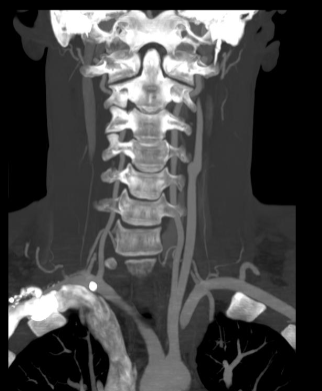

Wat is kenmerkend op CT scans?

Bot, disci, uittredende wortels

Wat is het verschil tussen een CT-botvenster en een CT-weke delen venster van de wervelzuil?

Een CT-botvenster verhoogt het contrast tussen verschillende botsoorten en zorgt voor optimale visualisatie van het trabeculaire en corticale bot. Een CT-weke delen venster optimaliseert het contrast voor structuren zoals spieren, disci en zenuwwortels, waardoor details van zachte weefsels beter zichtbaar zijn.